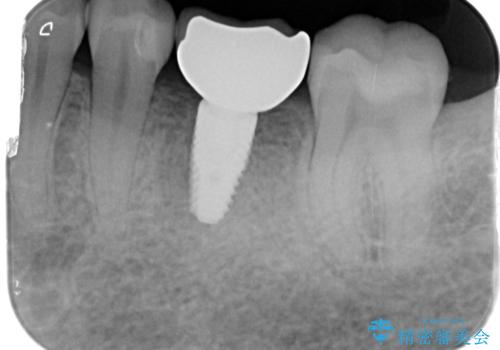

- 80万円(インプラント×2・骨造成・アバットメント×2)・ジルコニアクラウン×2)費用は治療当時の料金となります

インプラントの長期的な予後を見込むには、インプラント周囲の安定した十分な骨量や清掃性、角化歯肉の存在が重要です。